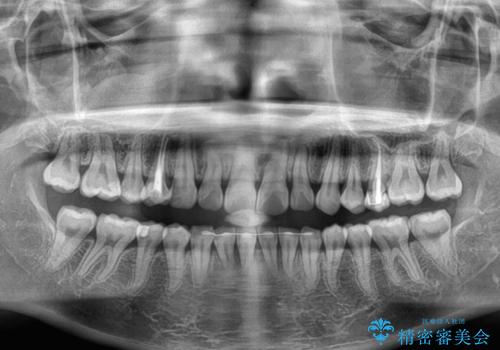

- デコボコの歯列が気になるとことで来院された患者様です。

歯列不正としては軽度であったため、インビザラインでもワイヤー装置でも対応可能でしたが、ご本人の希望によりインビザラインによる矯正治療を行うこととしました。

マウスピース矯正は、自己管理が非常に重要と事前にお伝えしておりましたが、毎日のマウスピース装着が遵守できず、ワイヤー装置での矯正治療へ変更することとなりました。

インビザラインからワイヤー装置へ変更すると、費用が追加となるため、ワイヤー装置は目立つものの費用を抑えることのできるメタルブラケットを使用しました。